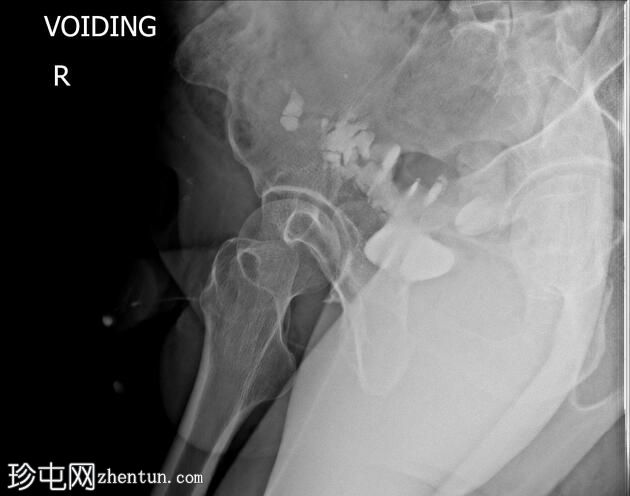

排尿困难。既往有膀胱癌病史及根治性膀胱切除术。

前列腺部、膜部、球部及阴茎部尿道均正常。

造影剂经尿道注入,开始充盈具有肠袢特征的新膀胱。

该患者确诊为移行细胞癌后行膀胱切除术。治疗方案包括根治性膀胱切除术及新膀胱重建术。